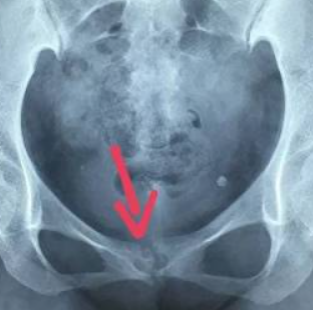

宝妈罗女士产后,出现“门户处”(耻骨联合区)疼痛不适,压痛明显,妇科超声检查未发现异常,考虑为产后并发症耻骨联合分离。

宝妈未引起重视,一个多月后,疼痛仍不能缓解且有加重趋势,遂来我院影像科拍骨盆DR片。

发现其耻骨联合间隙稍增宽,双侧关节面可见硬化、毛糙、囊性改变,考虑为耻骨联合骨软骨炎。采取对症治疗,疗效显著,症状得到明显改善。

1.X线摄影检查—最简便

主要影像表现有耻骨联合间隙正常或增宽,骨缘骨质硬化,部分囊变,多见于双侧,也可单侧;耻骨联合骨缘锯齿状、鼠咬状、虫蚀状骨质破坏,边缘不光整,有时可见游离小骨块,有时耻骨联合呈不同程度错位。